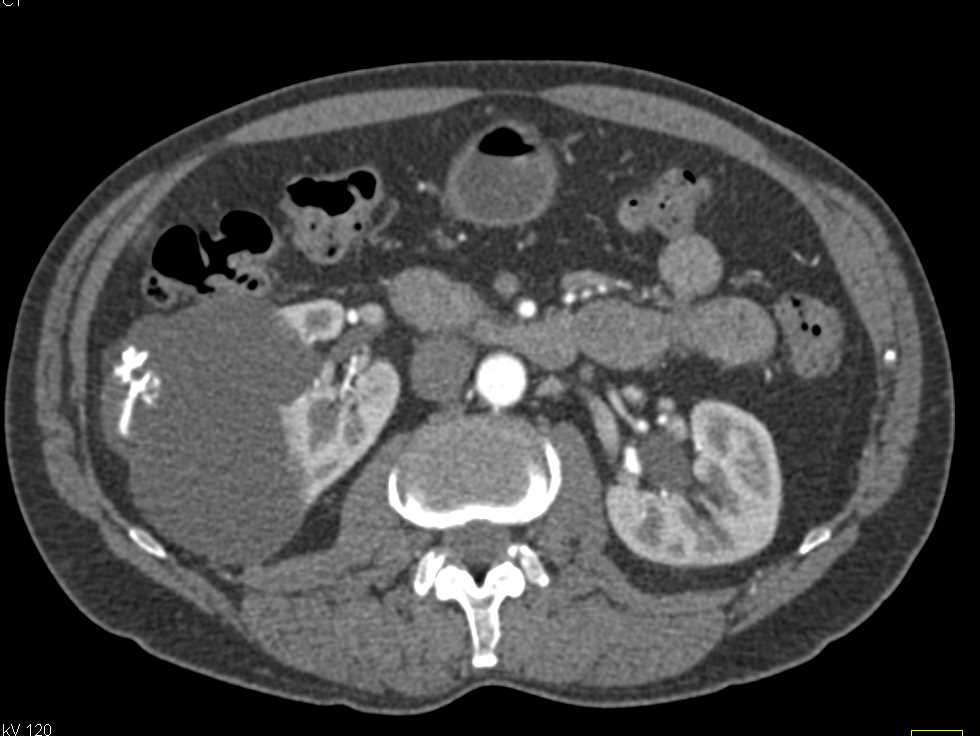

Complex Bosniak 2F Cyst